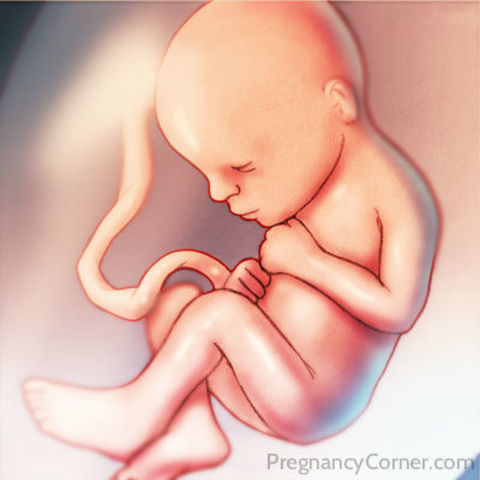

Week Eight Developments

The fetus is now about 12 mm in size. In addition, the teeth as well as the palate are starting to form in the fetus. Brain waves can also be detetected from the baby.